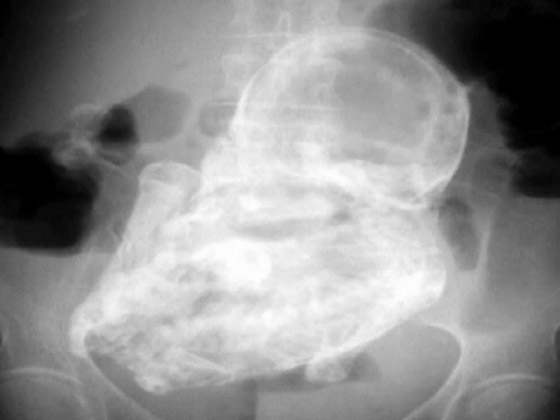

"اللي يعيش ياما يشوف".. ينطبق هذا المثل على واقعة شهدتها المكسيك وبطلتها كانت امرأة ثمانينية! فقد أدهشت السيدة-التي تبلغ من العمر 84 عاما من دورانجو بالمكسيك- المسعفين عندما اكتشفوا أن آلام البطن التي تشكو منها لم تكن إلا جنينا محنطا في رحمها منذ ما يزيد عن 4 عقود.

وبحسب ما ورد في صحيفة بريطانية، فإن المرأة ذهبت إلى عيادة الصحة العامة بسبب آلام مبرحة في بطنها، وبالفحص وجدوا أنها تحمل جنينا لم يكتب له أن يولد منذ 40 عاما. ويعتقد الأطباء أن الجنين قد تكلس، في حدث نادر للغاية يسمى "الجنين المتحجر أو المتكلس".

وعادة تنشأ الظروف المفجعة لهذه الحالة النادرة عندما يموت الجنين أثناء الحمل في البطن، ويكون كبيرا جدا بحيث لا يمكن للجسم امتصاصه، فيتكلس من الخارج كجزء من تفاعل جسم غريب، مما يحمي جسم الأم من الأنسجة الميتة للجنين ويقيها من العدوى.

ويعتقد المسعفون أن الطفل مات وتحنط في الأسبوع الأربعين من الحمل، بعد أن توقف عن النمو بشكل طبيعي. وأضافت التقارير أنه من غير المرجح أن تكون الأم قد تلقت الرعاية المناسبة في أثناء الحمل قبل حوالي 40 عاما.